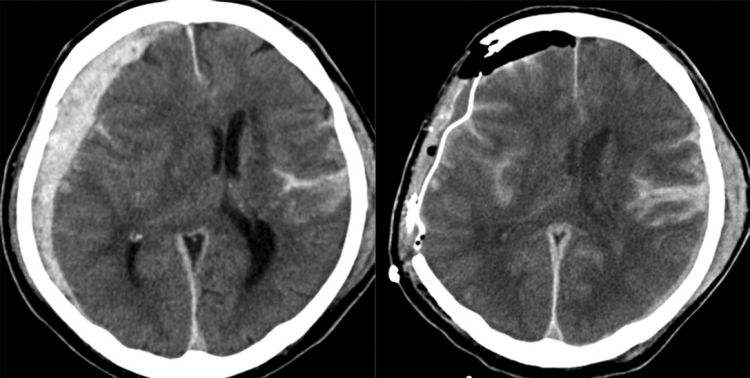

症状小脑幕切迹疝时,颅内压增高症状表现为剧烈头痛及频繁呕吐,其程度较在脑疝前更形加剧,并有烦躁不安意识改变表现为嗜睡浅昏迷以至昏迷,对外界的刺激反应迟钝或消失瞳孔改变表现为两侧瞳孔不等大,初起时病侧瞳孔略缩小,光反应...